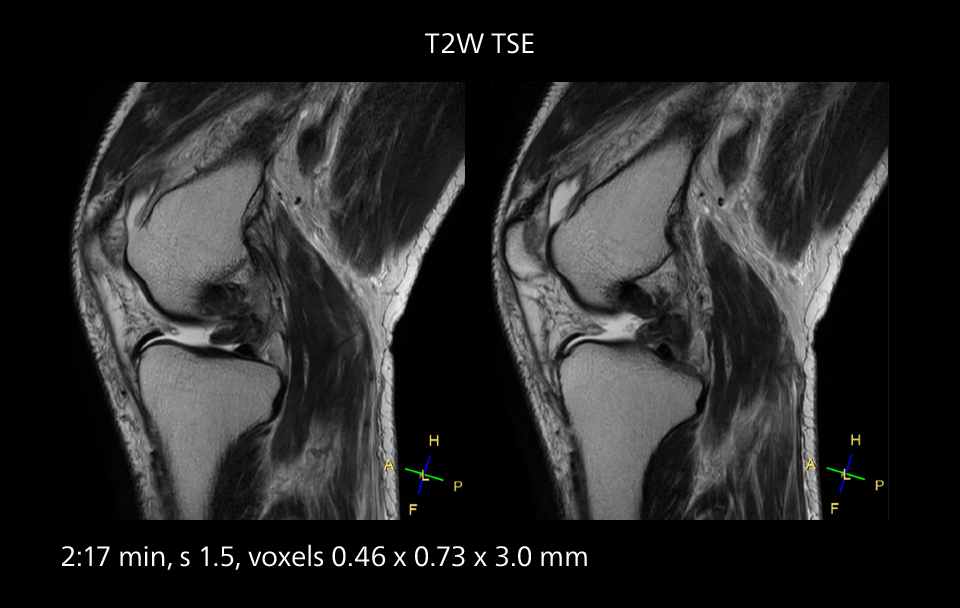

MRI of the knee

Images showing a posterior cruciate ligament (PCL) tear, a detached medial collateral ligament (MCL) on the tibial side and an intact anterior cruciate ligament (ACL). SmartPath to Elition X helped reduce scan time compared to previous imaging while maintaining resolution.